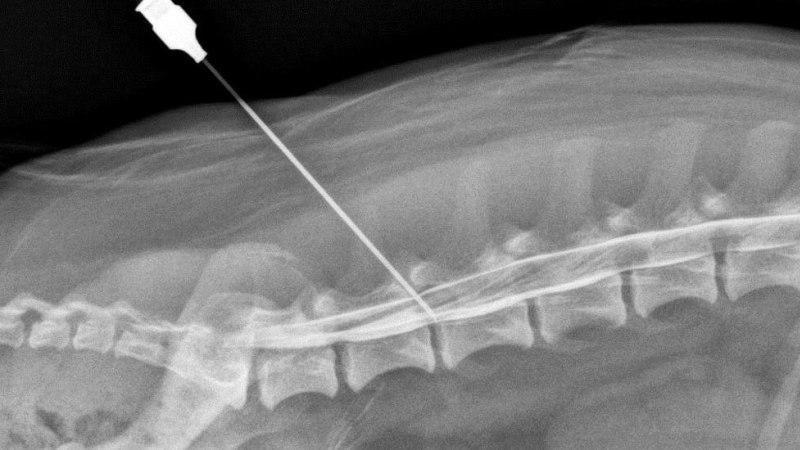

Обычно выполняется около 4-5 инъекций. Игла вводится до упора, а затем под углом (не извлекая ее полностью) препарат доставляется под отросток. Процедура проводится с использованием рентгеновского контроля, что позволяет минимизировать риск возможных осложнений.

Эпидуральная процедура

Во время выполнения эпидуральной процедуры анестезия вводится с использованием специализированного оборудования, такого как флюороскоп, и применяется контрастное вещество. Это позволяет отслеживать, как анестетик распределяется по позвоночным сегментам и достигает нервных корешков. Затем контрастное вещество попадает в кровоток. Обезболивающее средство вводится непосредственно в область, где ощущается наибольшая боль.